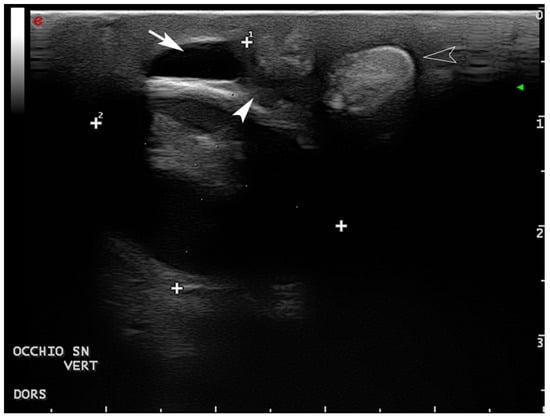

2.5. Diagnostic Imaging

- Mennonna, G.; Lamagna, B.; Affuso, A.; Greco, A.; Micieli, F.; Costanza, D.; Hochscheid, S.; Meomartino, L. Normal ultrasonographic features of loggerhead (Caretta caretta) eyes. Nat. Croat. 2020, 29 (Suppl. S1), 3–10. [Google Scholar]